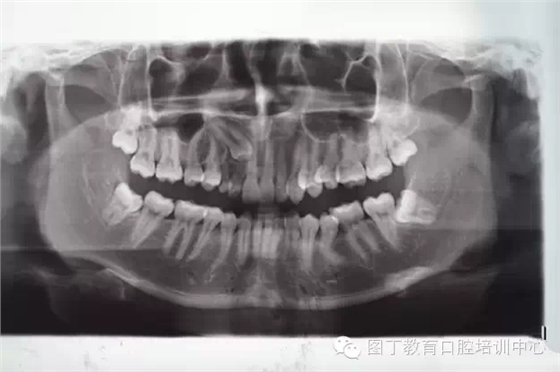

術(shù)前全景片檢查:13位于11、12根尖區(qū)。乳Ⅲ滯留。